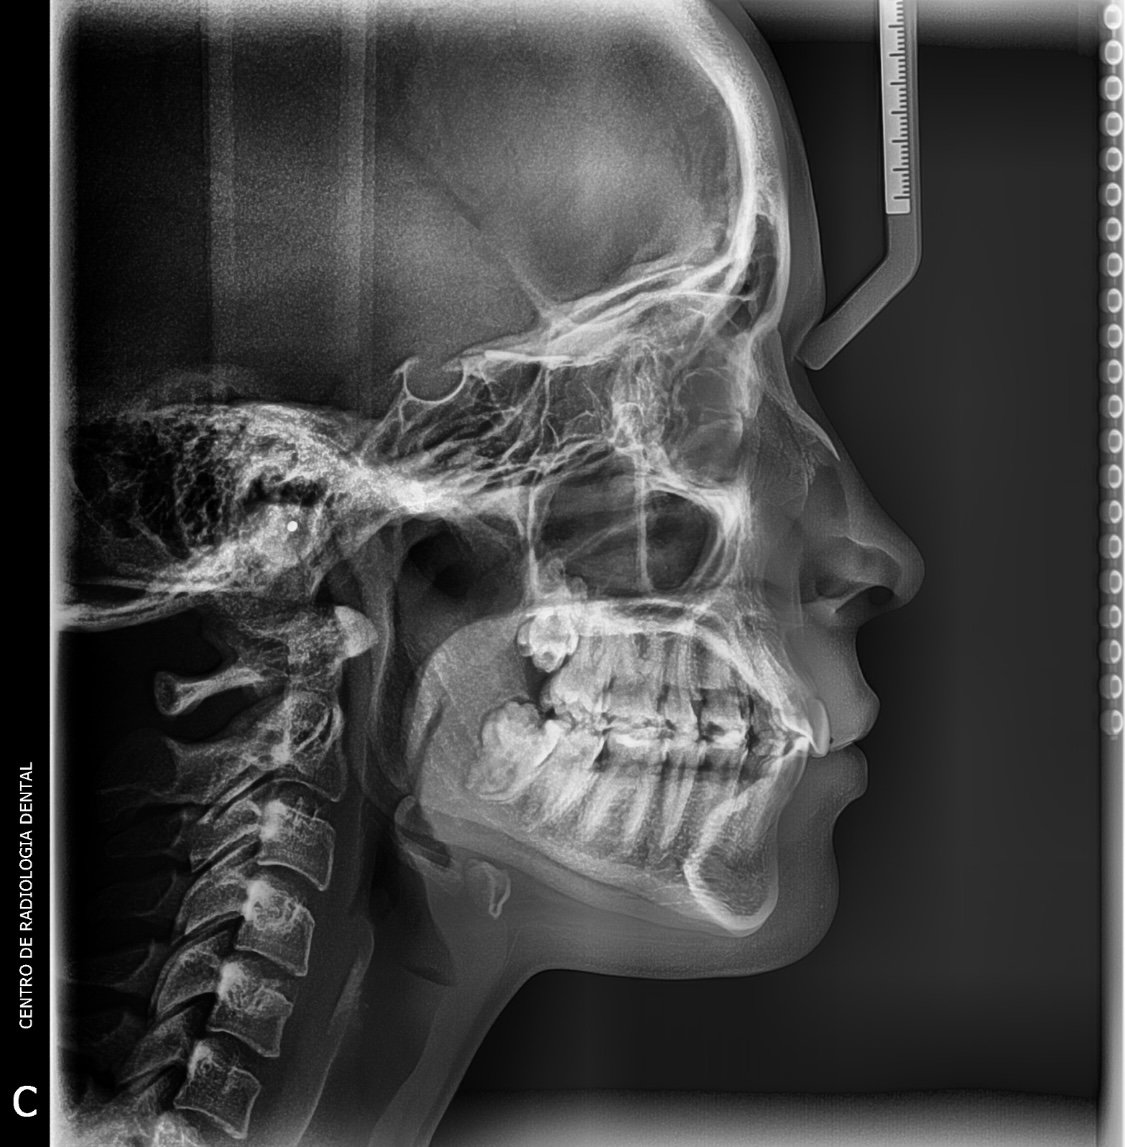

Imagen de Radiografía Lateral de Cráneo

Radiografía Lateral de Cráneo

Imagen de perfil del cráneo utilizada para realizar análisis de ortodoncia y planificación de cirugía ortognática. Permite medir las relaciones esqueléticas y dentales.

Costo: Consultar precio Duración: 10 min